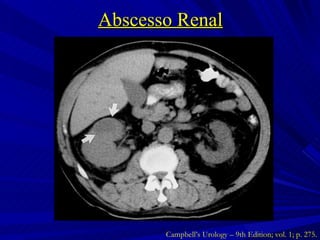

Abscesso Renal Coleção de material purulento confinado ao parênquima renal Inoculação hematogênica Gram + ( Staphylococci ) Formação no córtex renal  Infecção ascendente Gram – ( E. coli ) Formação na junção córtico-medular Campbell’s Urology – 9th Edition; vol. 1; p. 273 e 274.

Abscesso Renal Campbell’s Urology – 9th Edition; vol. 1; p. 275.

Abscesso Renal Tratamento  Abscessos < 3 cm ATB de amplo espectro direcionado à etiologia  Abscessos > 3 cm, imunodeprimidos ou falha do tratamento clínico Drenagem percutânea Campbell’s Urology – 9th Edition; vol. 1; p. 275 e 276.